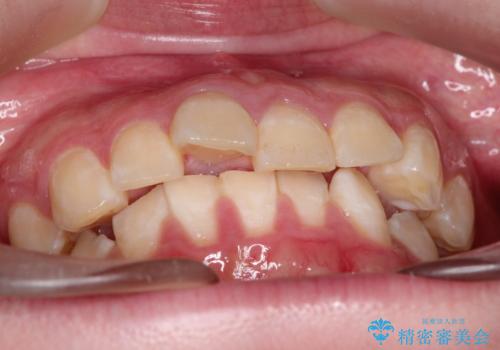

上下の歯のガタガタ ワイヤーでの抜歯矯正で整った歯並びへ

- 上下の歯のガタガタを治したいとのことで来院されました。

がたつきの度合いが強いのと、口元をなるべく引っ込めたい希望がありましたので、ワイヤーでの抜歯矯正となりました。

ガタガタが重度の方は抜歯が必要となることが多いです。

抜歯スペースを使って前歯を引っ込めることにより、口元の突出感も改善できました。